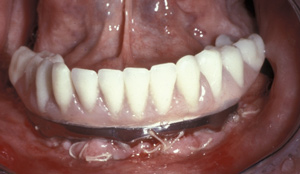

Fig 15. This all-resin interim restoration, which served as a fixed long-term provisional for more than 5 years, is an example of an entry-level option that offers the physiologic benefits of a long-term fixed restoration but with an economic equivalence to a mandibular two-implant overdenture.

Figure 15

Fig 16. This all-resin interim restoration, which served as a fixed long-term provisional for more than 5 years, is an example of an entry-level option that offers the physiologic benefits of a long-term fixed restoration but with an economic equivalence to a mandibular two-implant overdenture.

Figure 16

As an alternative to the relatively expensive traditional hybrid restoration that the senior population may perceive as unattainable at their age, an immediate-load all-resin provisional may often be a reasonable option as an entry-level prosthesis. This can serve for extended periods or indefinitely, and when made with a sufficient volume of resin and opposing a light occlusion such as a maxillary denture, it can offer the benefit of fixed retention at a significant reduction in expense (Figure 15 and Figure 16). Technology involving a guided approach for placing three implants universally in the same sites with pre-manufactured, one-size-fits-all bar components in the mandible can now allow placement of a final restoration in one day, again at a significantly reduced cost (Figure 17 and Figure 18).24-26 Both of these fixed options—the resin long-term provisional and the three-implant bridge—are economically comparable to the most commonly considered implant prosthesis for elderly patients, the two-implant overdenture. In contrast to the latter, however, both fixed restorations offer significant advantages in bite force, bone preservation, maintenance, and patient satisfaction that are simply unachievable with the removable implant overdenture prosthesis.27-31